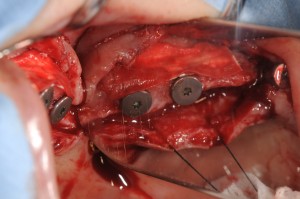

その後、仮歯を4本のインプラント支えながら、両側の骨のない部位に骨造成と同時のインプラント埋入を2回に分けて行いました。

上顎洞の側壁を開窓して、剥離した粘膜の下に静脈血から作成したCGFをいれて、その下に骨補てん材を入れます。

ここでも、ストローマンのSLActiveを使用します。

右上4,6部位への埋入。

左上は4,5部位への埋入。